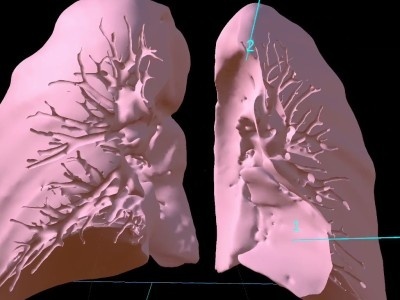

今回の授業ではこの1年間に習った内臓や筋、血管や神経といった臓器がどのように体内に存在し、その内部構造がどうなっているのかを、VR(3次元の仮想空間)で理解していきます。

しかし、このVRを用いた授業では、「へえ~」「なるほど」と仮想空間にある臓器を持ったり、位置の確認をしたり、のぞき込んだりと楽しく授業を受けていました

- 肺